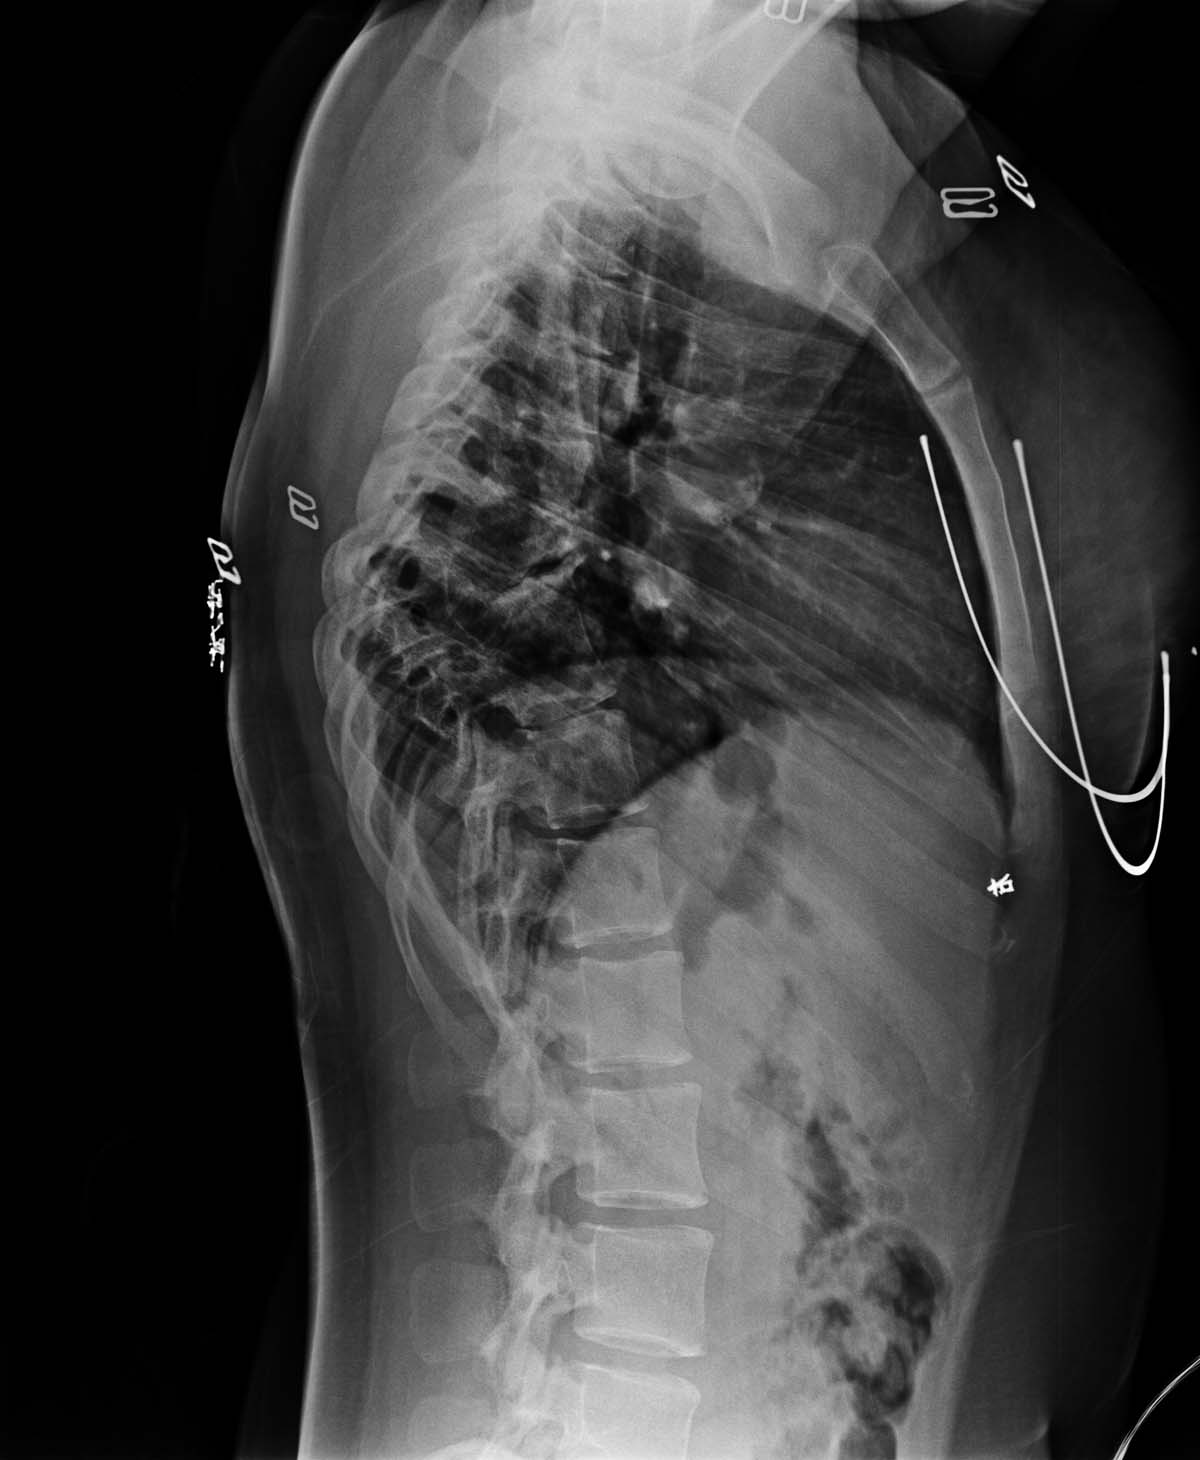

标题: X2233:胸椎结核是否活动?

女,19岁,2岁时胸椎结核,无手术,服药后愈合。具体不详。现背部痛。胸椎结核是否活动?